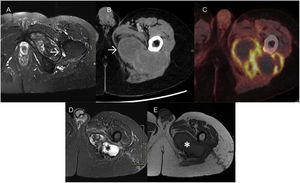

MRI images from this period show a homogeneous collection, markedly hyperintense on T2-weighted images, which fluctuates slightly in size, suggestive of postoperative seroma (Fig. 1A).

A) Axial T2-weighted image: hyperintense collection, with discrete variations in size over seven years, compatible with seroma. B) Ultrasound: lobulated lesion with well-defined borders, with a thick peripheral capsule and markedly heterogeneous content, without vascularisation on colour Doppler study. C) Axial T1-weighted image: increased signal intensity on T1-weighted sequences (*), corresponding to methaemoglobin and images compatible with clots. Peripheral capsule of tissue that is most likely fibrotic, markedly hypointense on all pulse sequences (→). D) MRI three months later; decreased signal on T1-weighted sequences suggesting subacute-chronic evolutionary changes of methaemoglobin, as well as mild clot growth. Hypointense peripheral capsule (→). E) The PET-CT study shows increased peripheral glucose metabolism, suggestive of an inflammatory process.

The patient reported pain during follow-up. An ultrasound (Fig. 1B) and an MRI (Fig. 1C) were performed, revealing a significant enlargement of the collection and findings compatible with rebleeding.

The MRI was repeated three months later (Fig. 1D), and the collection appeared more organised with septa, subacute-chronic evolutionary changes in methaemoglobin and slight growth of the clots.

PET-CT imaging revealed increased peripheral glucose metabolism, suggestive of an inflammatory process (Fig. 1E).